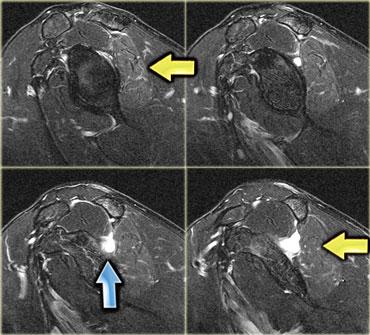

Hình bên trái là một bệnh nhân viêm đa cơ (PM), một trong các thể bệnh cơ viêm.

Các cơ lớn ở gốc chi bị tổn thương, thường theo hình thái đối xứng.

Nhìn chung, không phải tất cả các cơ đều bị tổn thương, do đó MRI có thể giúp xác định vị trí tốt nhất để sinh thiết.

Đôi khi MRI toàn thân được sử dụng để chẩn đoán và theo dõi viêm đa cơ sau khi đã bắt đầu điều trị bằng corticosteroid.